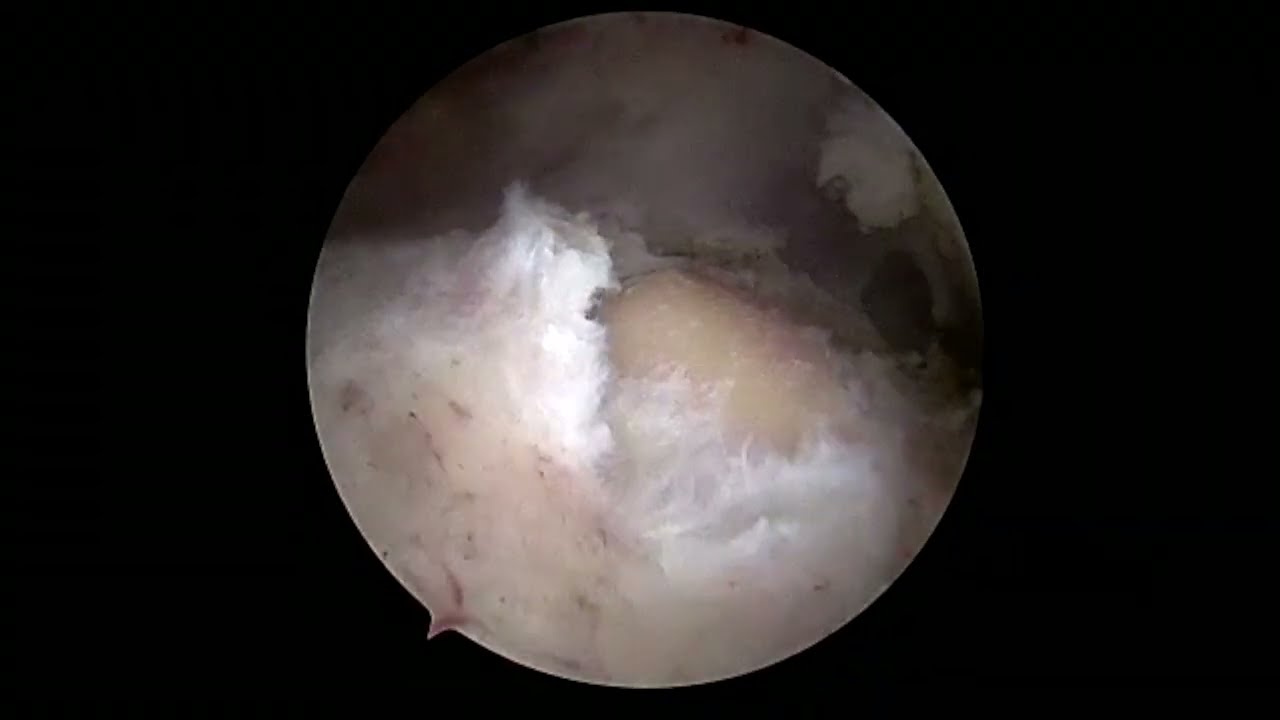

Arthroscopic Rotator Cuff Repair with a Double-Row Technique